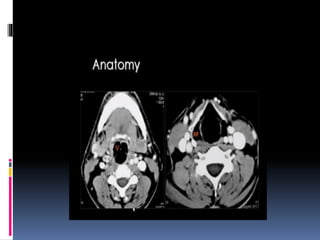

AXIAL SCANS

 Axial scans are best read from inferior to

superior.

 N.L.D., anteroposterior deviations of septum

and nasopharynx can be studied well in Axial cuts